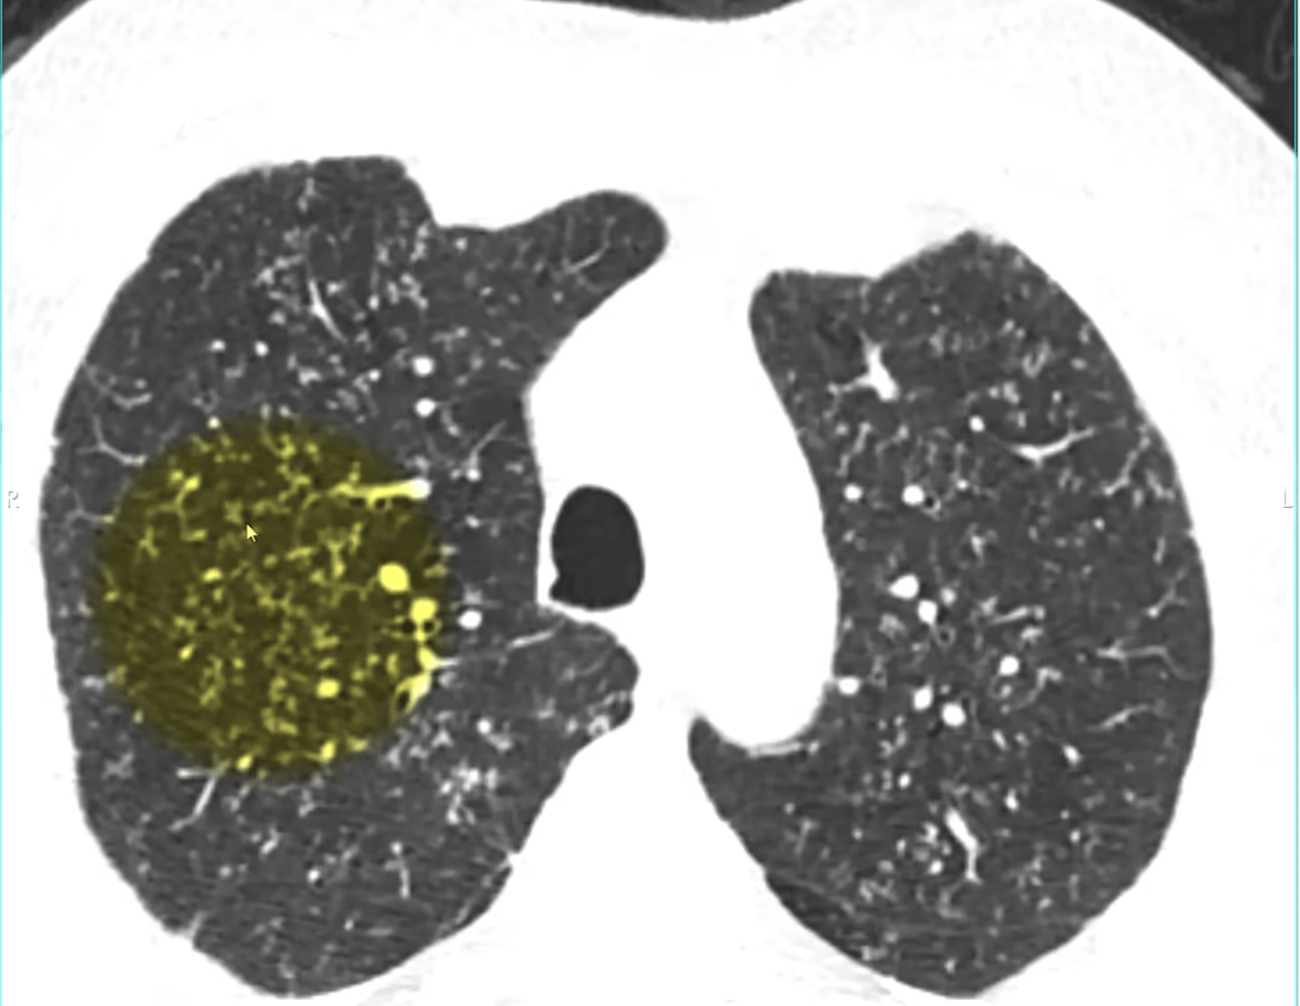

| | | History: Elderly man who presented with hematuria.